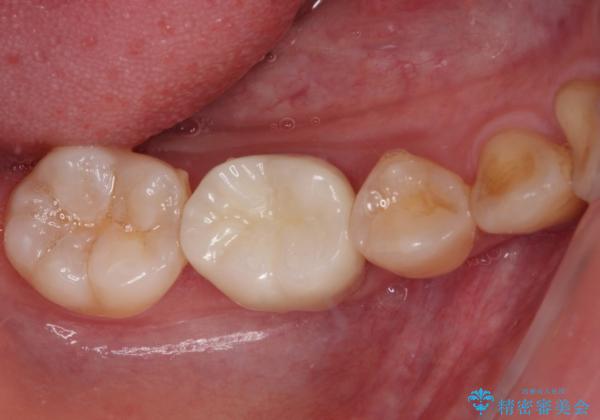

速やかに処置を進めたことで症状は落ち着き、治療後しばらくの状態では神経を取り除く可能性は低くなりました。